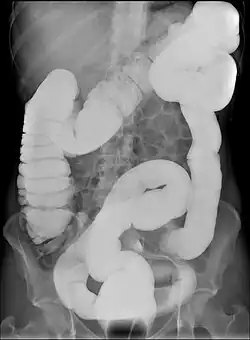

| Abdominal X-ray image with bowel contrast agent showing dolichocolon | |

Dolichocolon, also known as redundant colon or tortuous colon, is the congenital presence of an abnormally-long large intestine.[1] It should not be confused with an abnormally wide large intestine, which is called megacolon. The name originates from Ancient Greek: δολιχός, romanized: dolĭkhós, lit. 'long, protracted', and "colon".

Dolichocolon may predispose to abnormal rotation of the colon (volvulus) and its interposition between the diaphragm and the liver (Chilaiditi syndrome). The exact cause remains unknown.[2] Dolichocolon is often an incidental finding on abdominal X-rays or in colonoscopy. It is not by itself a disease and as such requires no treatment if asymptomatic.